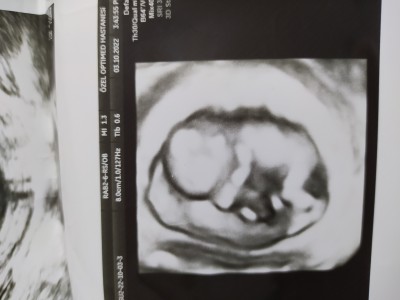

Kızlar diğer taraftan sordum fakat kapatıldı yoruma burdan da sorayım. 13+1 haftalık hamileyim bebeğimin cinsiyetini merak ediyorum yardımcı olabilir misiniz ilk hamileliğim

Erkek gibi göründü bana ama Allah'ın takdiri hayırlısı ile al kucağına rabbim yar ve yardımcın olsun inşallah canım

Sankii erkek..

Kesin sonuç alınca haber ver bana bakalım bana göründüğü gibi erkek mi bebeto

Kız hissettim ben de